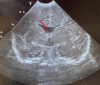

Figure 1

Transfontanellar ultrasound performed on the second day of life, in which the pellucid septum is absent (arrow).